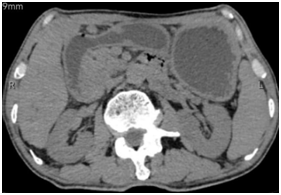

患者4年前确诊肝内胆管癌,行手术治疗。近1月出现反复恶心、呕吐,症状逐渐加重,不能进食,营养状况急剧恶化,严重影响患者的生活质量及疾病治疗。腹部CT考虑肿瘤复发导致十二指肠梗阻,胃潴留。消化内科刘鹏飞主任团队认真评估患者病情,并与患者及家属充分沟通后,决定实施先进的超声内镜技术EUS-GE,通过放置支架连通胃与肠道,为患者解决不能进食的困扰。

图1:可见肿瘤压迫十二指肠导致严重胃潴留